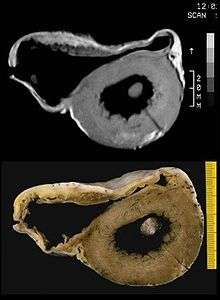

Fatty infiltration of the RV free wall can be visible on cardiac MRI. Fat has increased intensity in T1-weighted images. However, it may be difficult to differentiate intramyocardial fat and the epicardial fat that is commonly seen adjacent to the normal heart. Also, the sub-tricuspid region may be difficult to distinguish from the atrioventricular sulcus, which is rich in fat.

Cardiac MRI can visualize the extreme thinning and akinesis of the RV free wall. However, the normal RV free wall may be about 3 mm thick, making the test less sensitive.

A biopsy sample that is consistent with ARVD would have > 3% fat, >40% fibrous tissue, and <45% myocytes.

A post mortem histological demonstration of full thickness substitution of the RV myocardium by fatty or fibro-fatty tissue is consistent with ARVD.